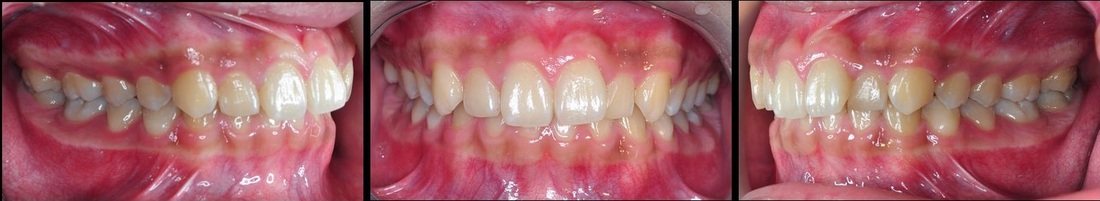

張小弟前來問診前,認為自己是暴牙的問題,與蔡醫師討論過後,原來是下顎較短,下巴較短,導致看起來有暴牙的狀況

蔡醫師讓張小弟戴上『活動式功能矯正器』,

這是可拆式的,

主要是促進下顎的生長,補足下顎的發育不完全。

上圖:下顎短小,有深咬的情況,病患會誤以為暴牙。

下圖:經過五個月的時間,張小弟的咬合情況已改善不少。